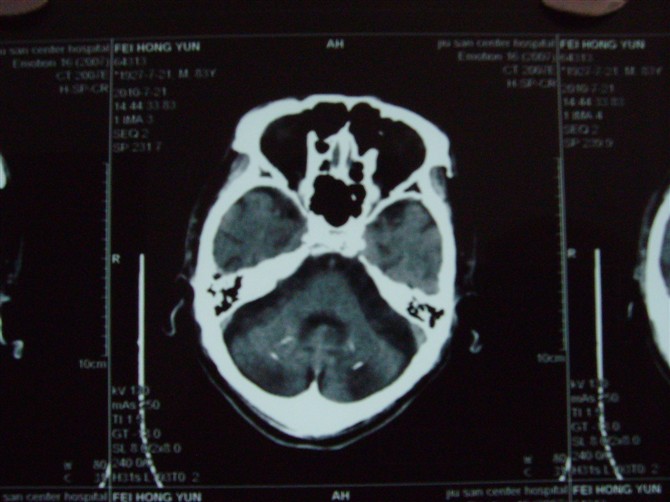

标题: CT27993:男 83岁 头晕伴双下肢无力一天 [打印本页]

标题: CT27993:男 83岁 头晕伴双下肢无力一天

脑萎缩。伴小脑齿状核、苍白球钙化。必要是mri进一步检查。

脑萎缩。伴小脑齿状核、苍白球钙化.脑白质脱髓鞘病变

脑白质变性、脑萎缩。甲状旁腺功能减退。

1)双侧小脑半球脑软化灶。2)全脑萎缩。3)脑白质病。